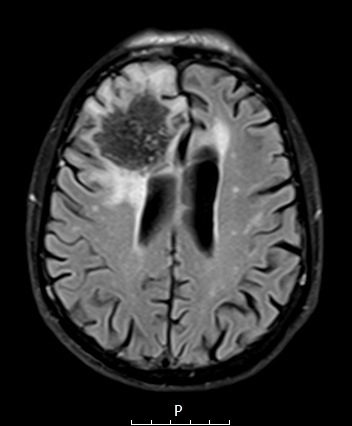

Case 7 History ---- The patient was an 84yo male who was in his usual state of health until February 2023 when he developed new onset neurologic symptoms/signs, most notable for personality changes, labile mood, impaired cognition, and imbalance. One week later, he had a first-time grand mal seizure with a second occurrence in the ED and was hospitalized for further investigation and management. He was intubated and briefly required mechanical ventilation for airway protection. MRI revealed a 5 cm right frontal mass with mild vasogenic edema and mass effect. He received a few days of steroids, and anxiolytics/antipsychotics as needed for agitation. Procedure: Stereotactic brain biopsy. ---- 7A1-5 MRI scans ---- 7A1 The impressive lesion is hypointense with surrounding bright edema on T2 FLAIR.